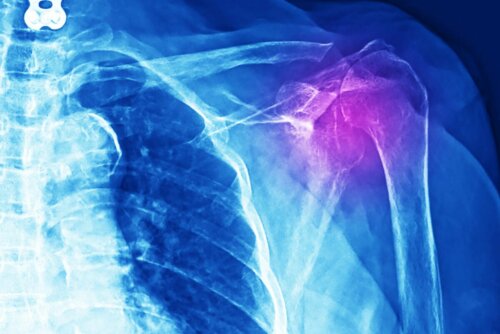

No diagnóstico dessa lesão, são realizados diversos exames que incluem radiografia, ultrassonografia e ressonâncias, e até mesmo a tomografia axial computadorizada (TC). Além disso, é feito um exame médico clínico e um estudo detalhado do histórico médico do paciente.